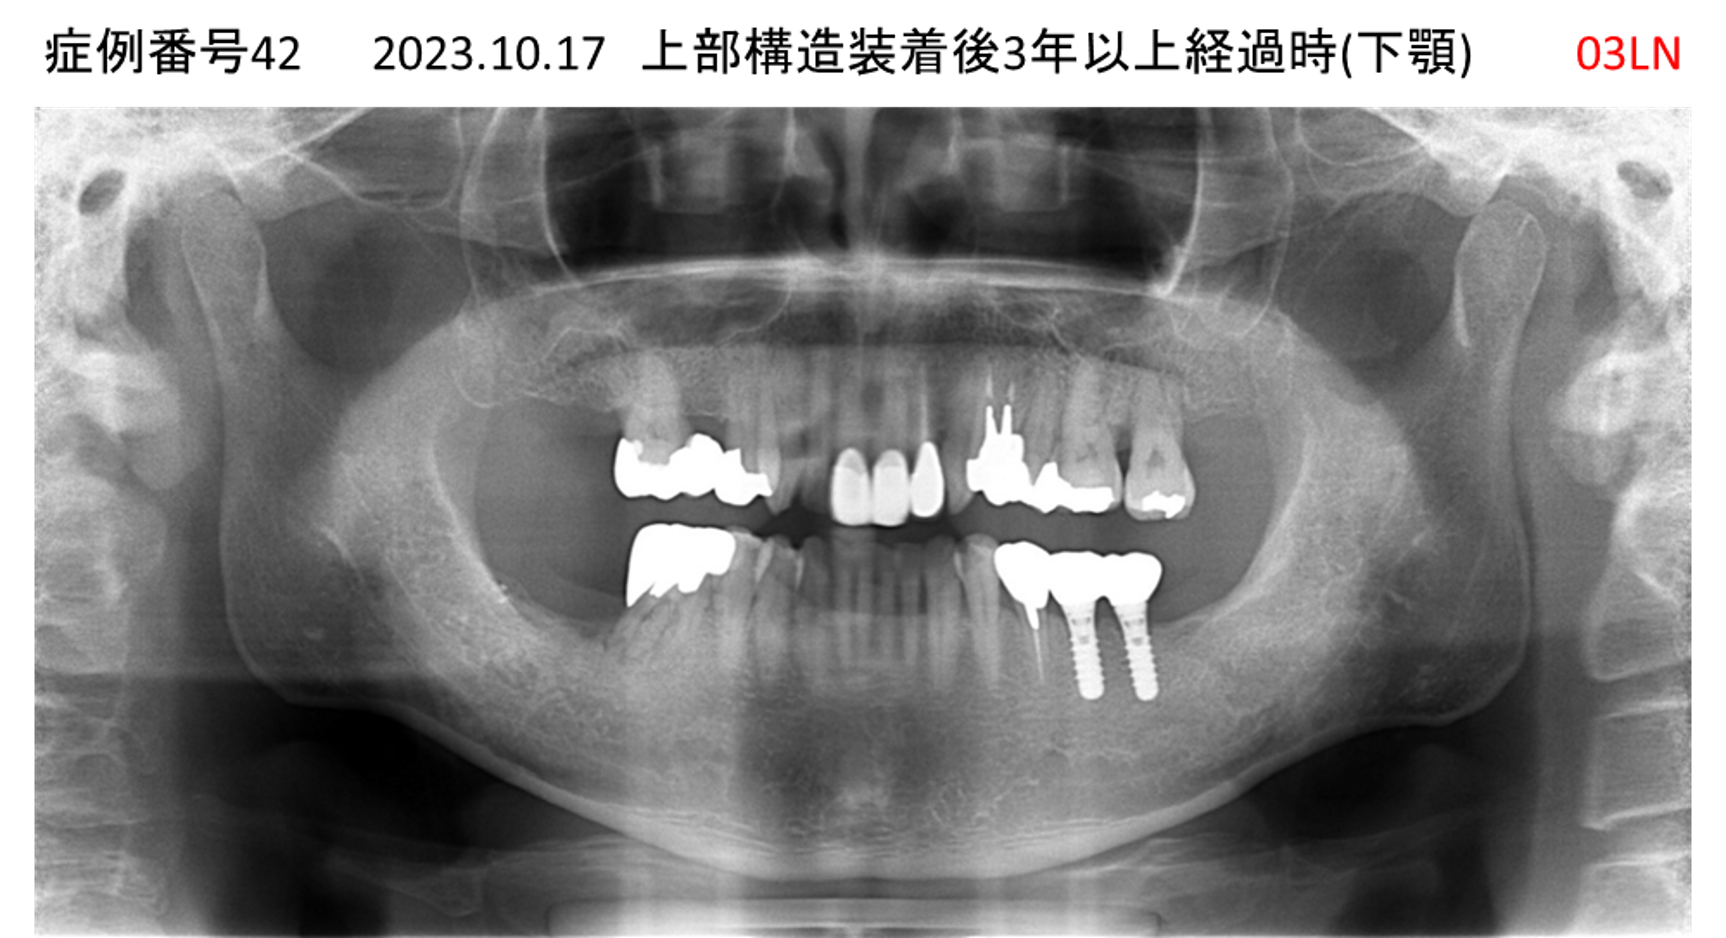

奥歯で噛めない患者様のインプラント症例

| 治療名称 |

インプラント |

| 治療費用 |

365万円+税 |

| 治療期間 |

5か月 |

| 患者さんの症状(主訴) |

奥歯で噛めない。上の前歯が揺れてきた。 |

| 治療内容 |

抜歯即時インプラント |

| 治療結果 |

食事に困らない。見た目がとても良くなった。 |

| 治療の注意点(リスク/副作用) |

インプラントが壊れたら再治療が必要 |